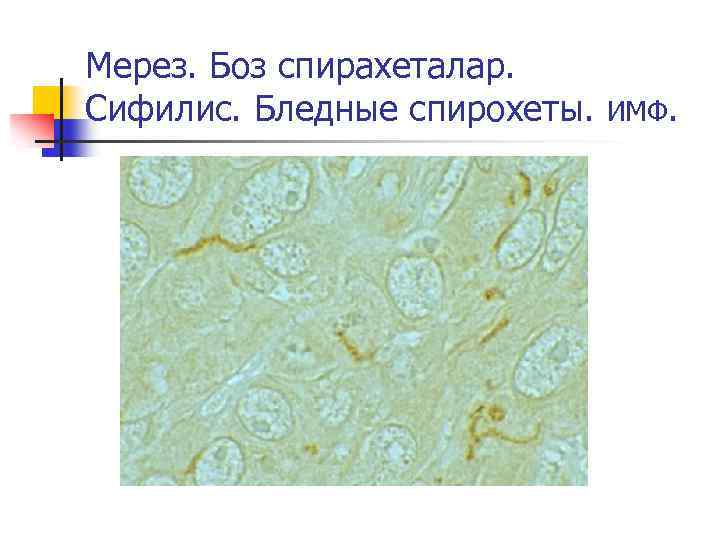

Мерез. Боз спирахеталар. Сифилис. Бледные спирохеты. ИМФ.

Мерез. Боз спирахеталар. Сифилис. Бледные спирохеты. Күмістендіру.